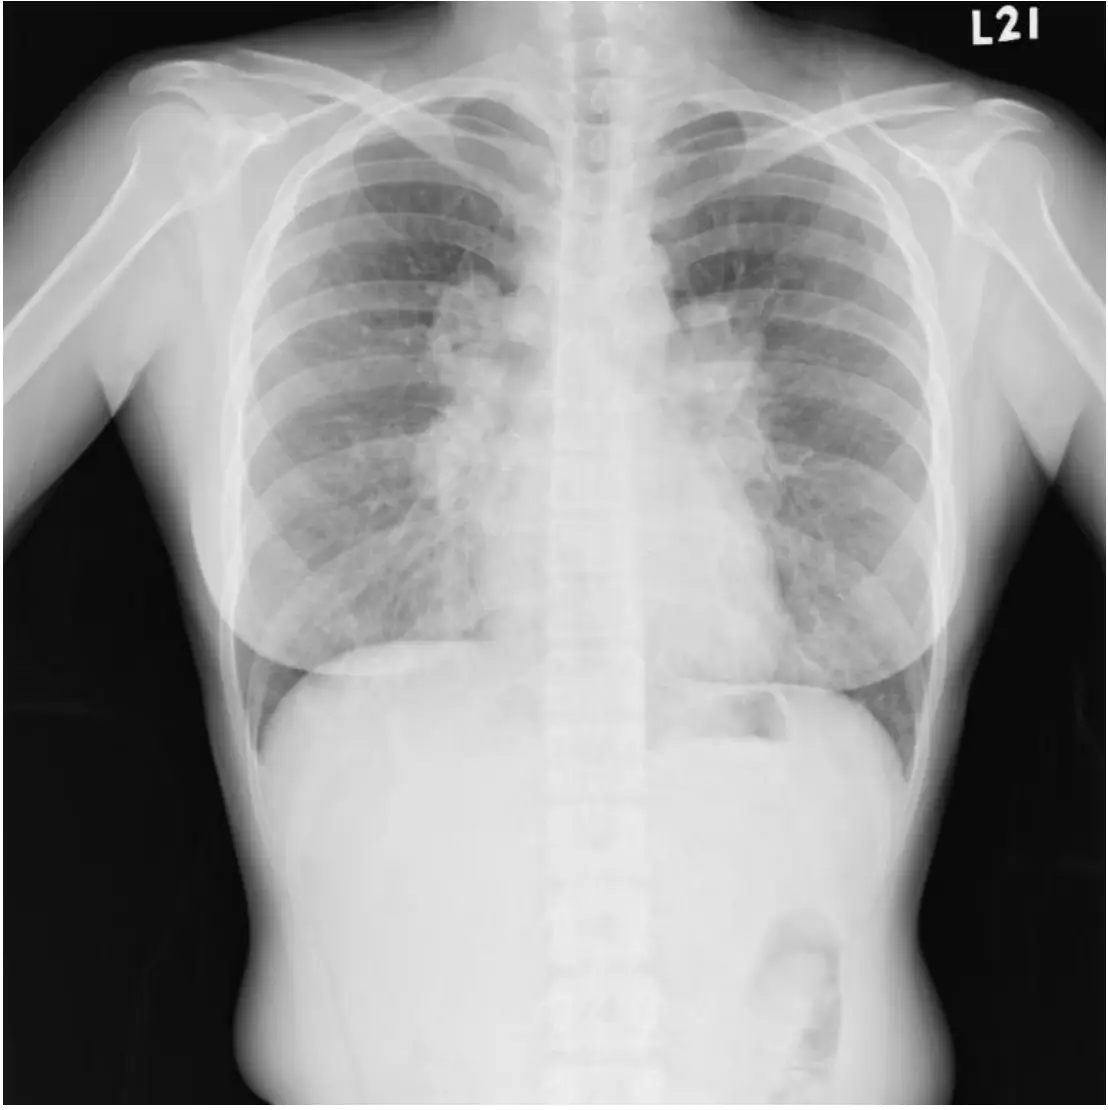

圖:胸部 X 光(Chest X-ray,PA view)

本圖為站立位後前位(posteroanterior)胸部 X 光:

- 雙側肺門對稱性腫大(bilateral hilar lymphadenopathy, BHL):雙側肺門陰影顯著擴大且左右對稱,此為結節病最典型的 X 光表現。右側肺門旁可見伴隨之氣管旁淋巴結腫大(right paratracheal lymphadenopathy),呈現「1-2-3 sign」或「Pawnbroker sign」的特徵輪廓。

- 肺實質(lung parenchyma):雙肺野清晰,無明顯浸潤、結節或纖維化,提示病灶僅限於縱膈腔及肺門淋巴結,尚未侵犯肺實質。

- 心臟大小及輪廓:正常範圍內,無心臟擴大。

- 肋膜腔:無積液。

X 光分期判讀:Stage I 結節病(雙側肺門淋巴結腫大,無肺實質浸潤)